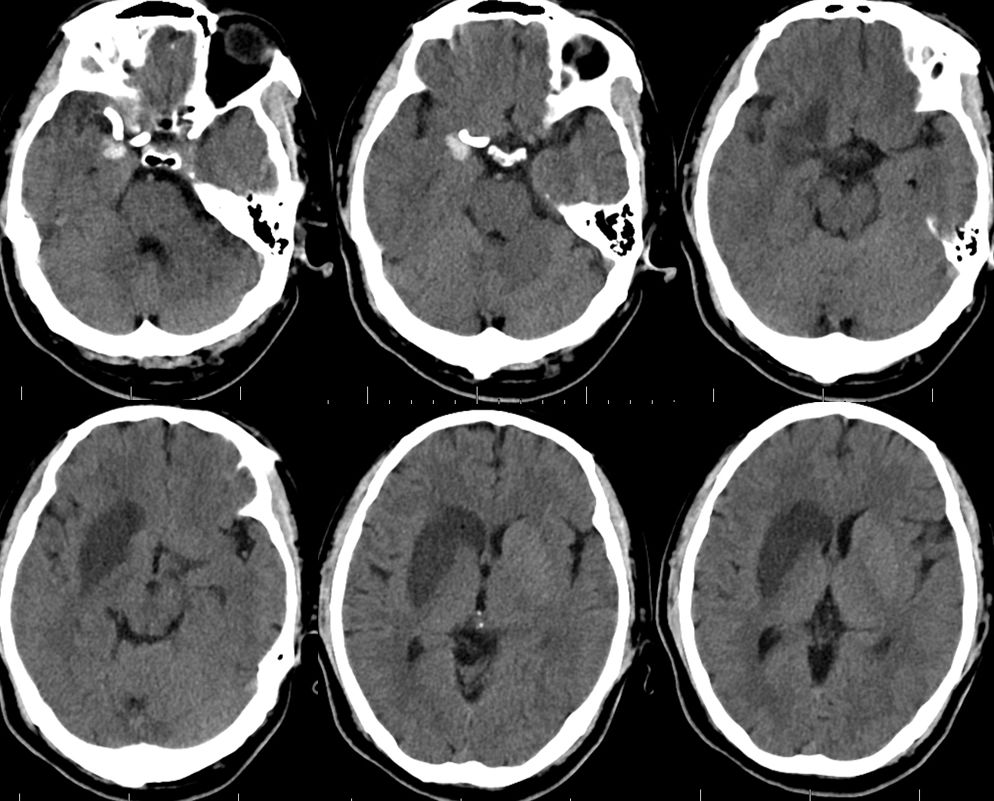

1、术后18小时CT(图五)。

图五

2、术后18小时急诊DSA(图六)。

图六

DSA术前后对比(图七)。

图七

术后3天CT(图八)。

图八